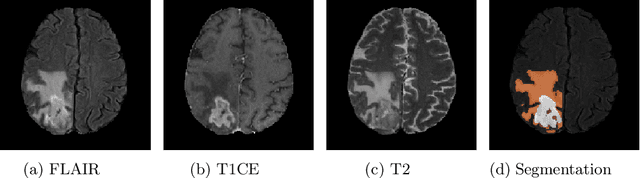

Abstract:Glioma, the malignant brain tumor, requires immediate treatment to improve the survival of patients. Gliomas heterogeneous nature makes the segmentation difficult, especially for sub-regions like necrosis, enhancing tumor, non-enhancing tumor, and Edema. Deep neural networks like full convolution neural networks and ensemble of fully convolution neural networks are successful for Glioma segmentation. The paper demonstrates the use of a 3D fully convolution neural network with a three layer encoder decoder approach for layer arrangement. The encoder blocks include the dense modules, and decoder blocks include convolution modules. The input to the network is 3D patches. The loss function combines dice loss and focal loss functions. The validation set dice score of the network is 0.74, 0.88, and 0.73 for enhancing tumor, whole tumor, and tumor core, respectively. The Random Forest Regressor uses shape, volumetric, and age features extracted from ground truth for overall survival prediction. The regressor achieves an accuracy of 44.8% on the validation set.

Abstract:Brain tumor segmentation intends to delineate tumor tissues from healthy brain tissues. The tumor tissues include necrosis, peritumoral edema, and active tumor. In contrast, healthy brain tissues include white matter, gray matter, and cerebrospinal fluid. The MRI based brain tumor segmentation research is gaining popularity as; 1. It does not irradiate ionized radiation like X-ray or computed tomography imaging. 2. It produces detailed pictures of internal body structures. The MRI scans are input to deep learning-based approaches which are useful for automatic brain tumor segmentation. The features from segments are fed to the classifier which predict the overall survival of the patient. The motive of this paper is to give an extensive overview of state-of-the-art jointly covering brain tumor segmentation and overall survival prediction.

Abstract:The paper demonstrates the use of the fully convolutional neural network for glioma segmentation on the BraTS 2019 dataset. Three-layers deep encoder-decoder architecture is used along with dense connection at encoder part to propagate the information from coarse layer to deep layers. This architecture is used to train three tumor sub-components separately. Subcomponent training weights are initialized with whole tumor weights to get the localization of the tumor within the brain. At the end, three segmentation results were merged to get the entire tumor segmentation. Dice Similarity of training dataset with focal loss implementation for whole tumor, tumor core and enhancing tumor is 0.92, 0.90 and 0.79 respectively. Radiomic features along with segmentation results and age are used to predict the overall survival of patients using random forest regressor to classify survival of patients in long, medium and short survival classes. 55.4% of classification accuracy is reported for training dataset with the scans whose resection status is gross-total resection.